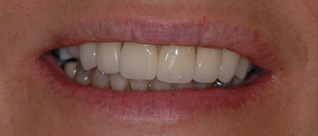

J’ai des problèmes, je refuse l’appareil mobile.

J’ai une maladie des gencives et mes dents tombent les une après les autres, je refuse un appareil que je serais obligé d’enlever

Solution : on va traiter les dents qui sont récupérables et remplacer les autres par des implants.

Implants multiples pour éviter les bridges et redonner des dents individuelles au patient avec traitement d’une maladie parodontale.

Implants multiples pour éviter les bridges et redonner des dents individuelles au patient. État final.